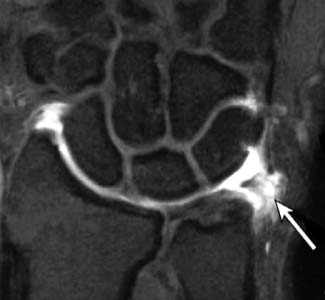

此圖為網路找到的手部MRI TFCC破裂照片(箭頭處)

白色很亮的地方為積水發炎